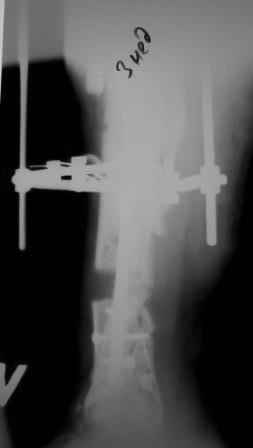

Коллеги!Позвольте продолжить обсуждение темы «ложный сустав левой голени.» Больной К 45 лет, начало см. http://www.weborto.net/forum/1228422607/ И рассказать о результатах проделанной работы. Остановились на следующей тактике 1) Наложить Аппарат Илизарова. В аппарате восстановить оси трех смещенных относительно друг-друга фрагментов большеберцовой кости. Устранить вальгусную деформацию дистального отдела большеберцовой кости. Что и было выполнено. - Была выполнена репозиция в аппарате (рис1) 2) После репозиции более очевидна стала проблема дефекта кости в верхней трети голени, два фрагмента свободно лежат. Остановились на варианте перехода на интрамедуллярный синтез стержнем с покрытием костный цемент+ванкомимцин и замещении дефекта с помощью транспорта фрагмента (рис 2) 3) Третьим этапом наложили модуль на промежуточный фрагмент.(рис 3) И начали его транспорт на стержне в проксимальном направлении. (рис 3 а) Надеемся что «вырастет» регенерат в дистальном отделе, а в проксимальном отделе фрагмент «упрется» и прирастет. Хочу сказать слова благодарности за обсуждение на форуме этого случая. Особые слова благодарности Иванову Павлу Анатольевичу!!! Он помогал Словом, а самое главное делом. Приезжал, оперировал! За что ему нижайший поклон! С ув Коробушкин Г